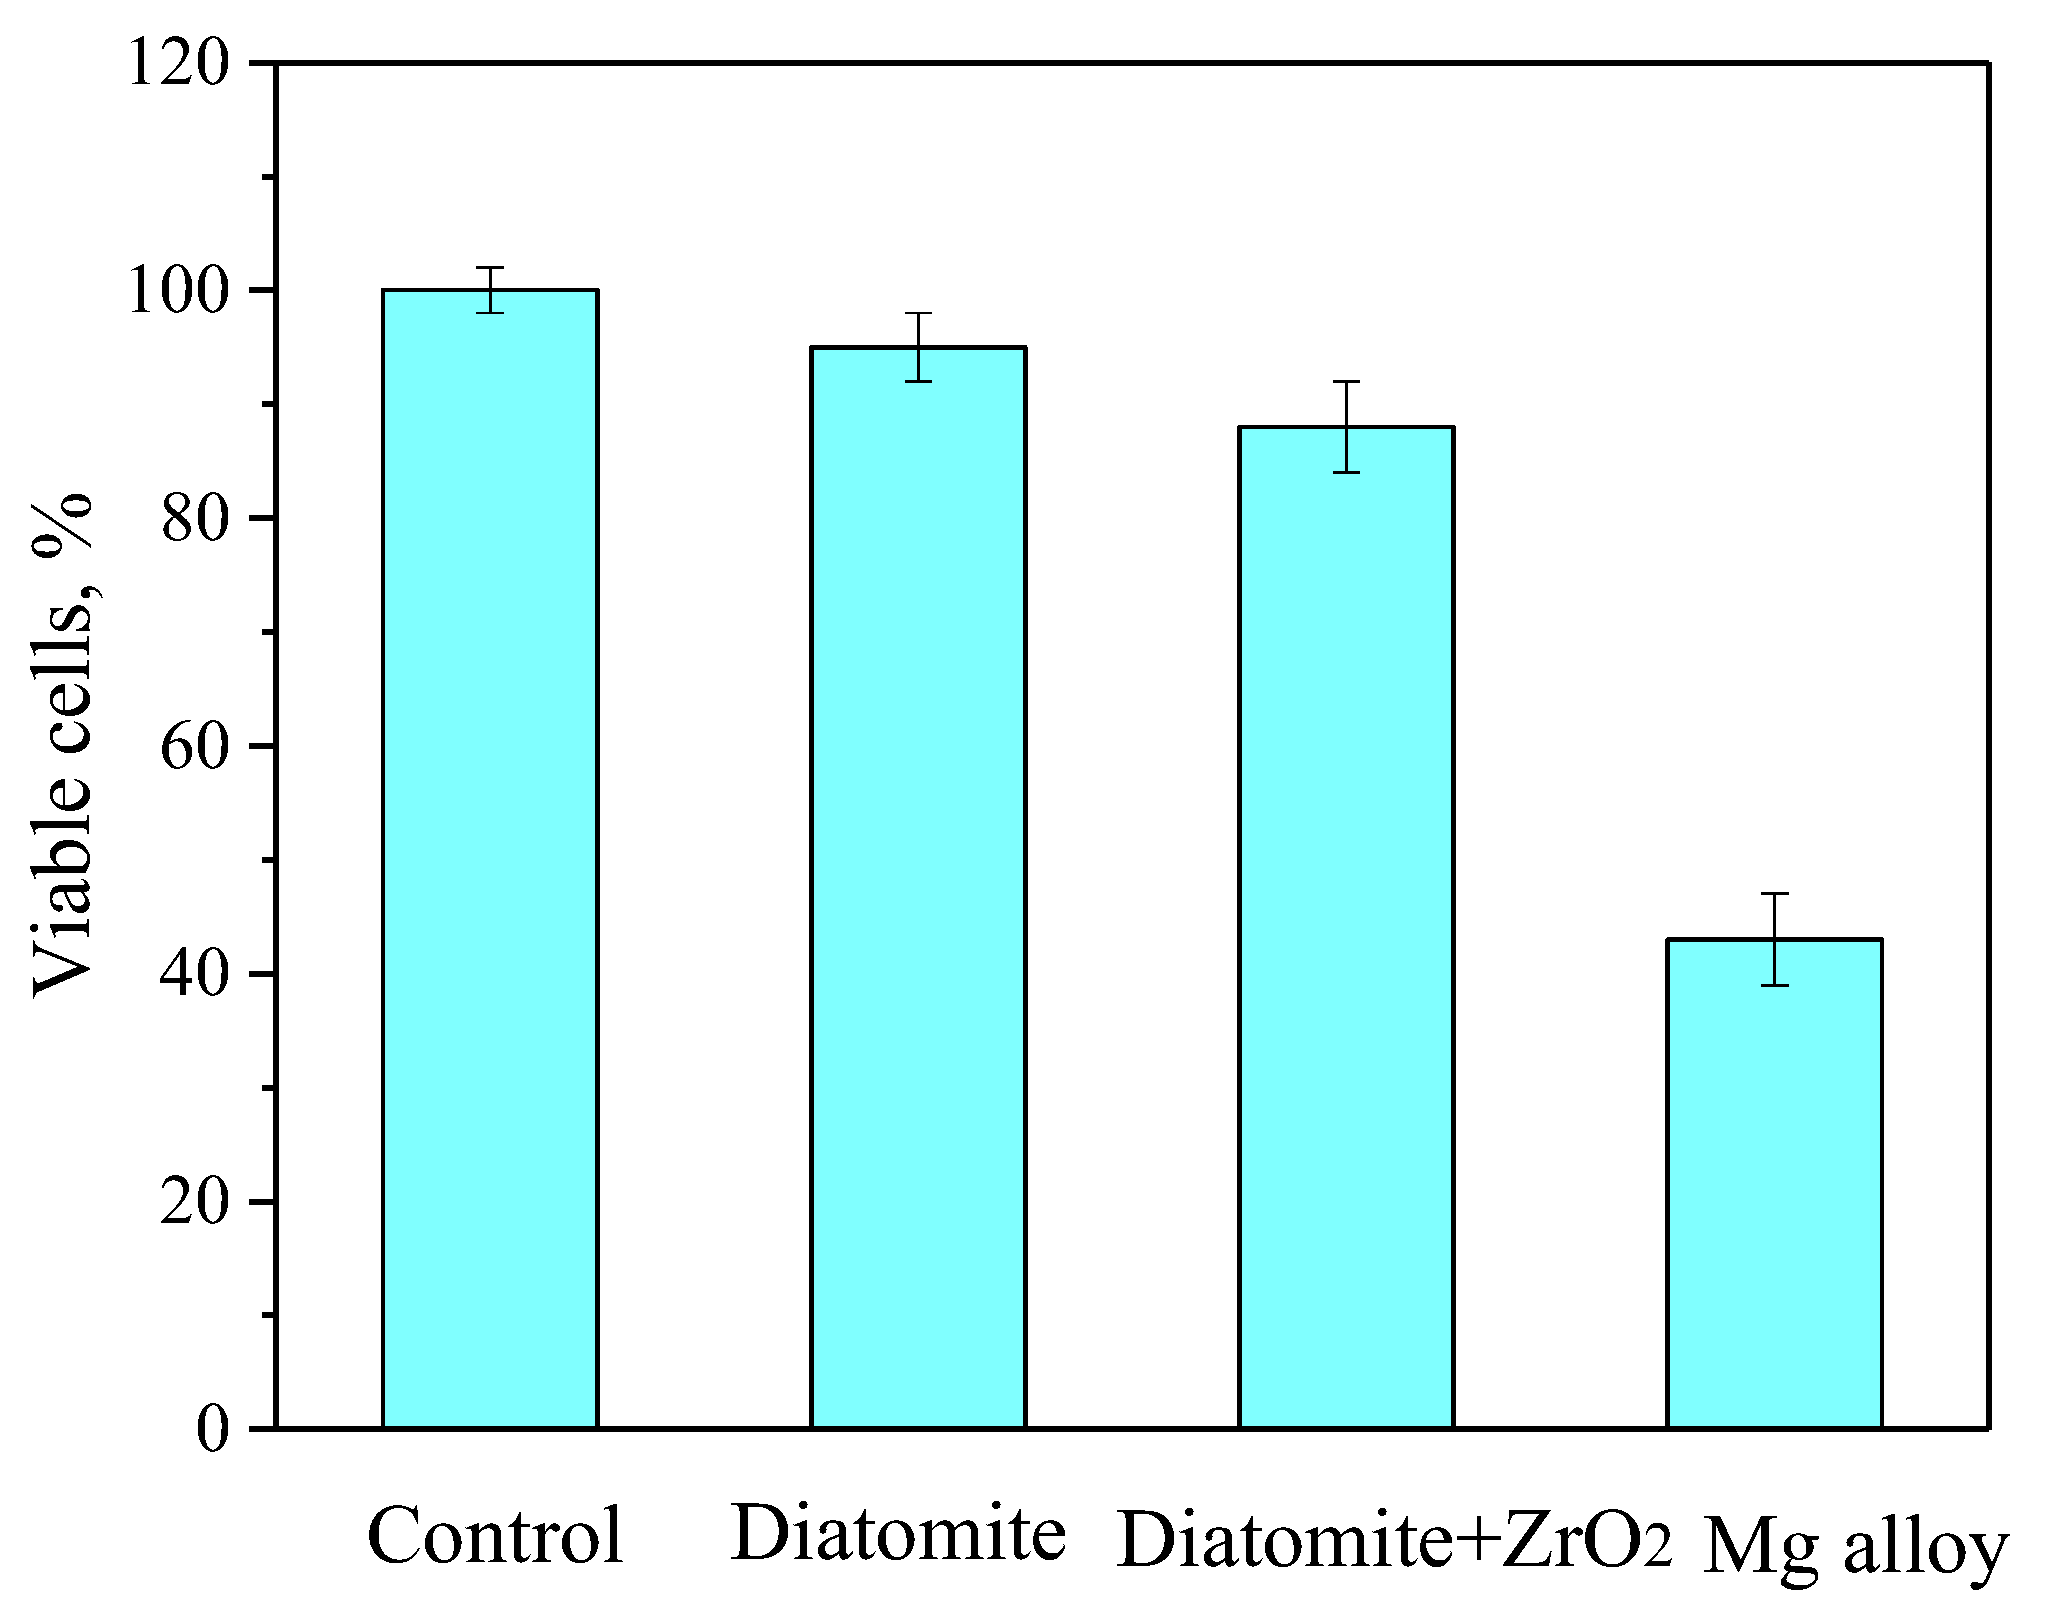

3.8. In Vitro Cytotoxic Assay